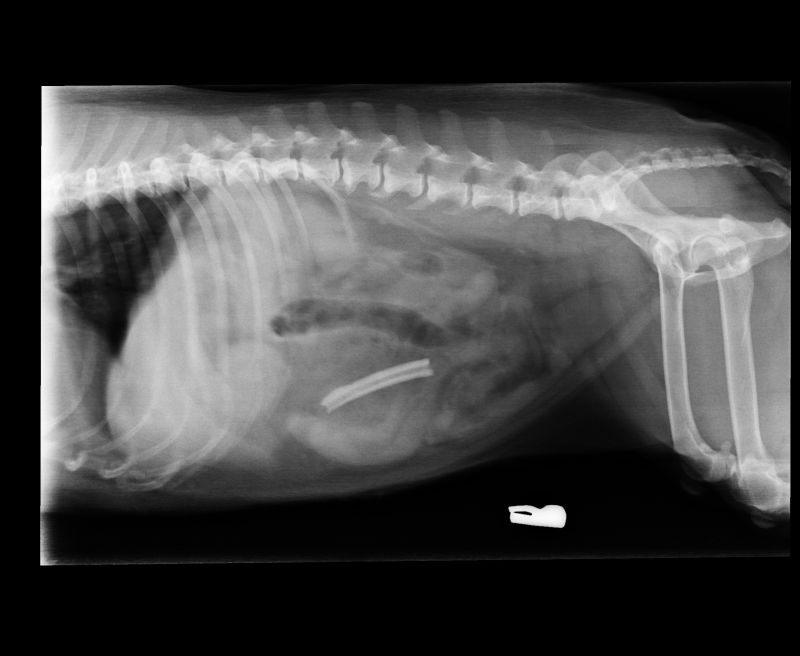

Abnormal Pathology on your pet

Shown on x-ray images which we have taken over the years.

Some interesting patient cases